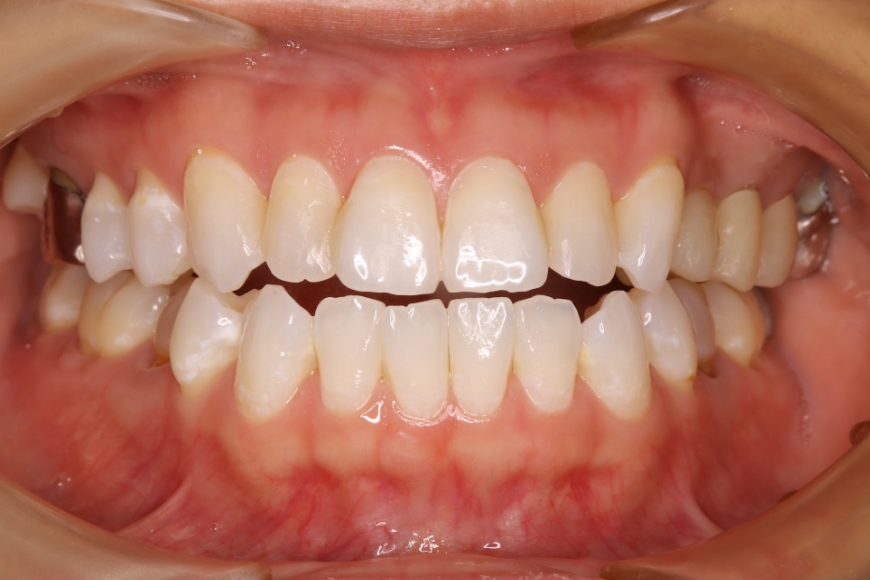

8歳男児 歯並びをきれいにしたい(保護者より)

治療前

治療後

治療内容 「がたがたの歯を治したい」と保護者と共に来院されました。

スペース不足による叢生(ガタガタの状態)と、前歯の見栄えが悪い状態でした。

床矯正装置にて2年程度歯列拡大を行い、永久歯の萌出誘導を行い、きれいな歯並びを獲得しました。

治療期間・回数 治療期間:約3年

通院回数:25~30回程度(成長段階に合わせた調整含む)

治療費用(総額)

242,000

(調整料込、治療時の金額であり、時期や手法により異なる場合があります。)

副作用・リスク ・顎の成長後に後戻りが起こる可能性があります。

・予定より治療期間が長くなることがあります。

・2期治療(大人の矯正)に移行することがあります。